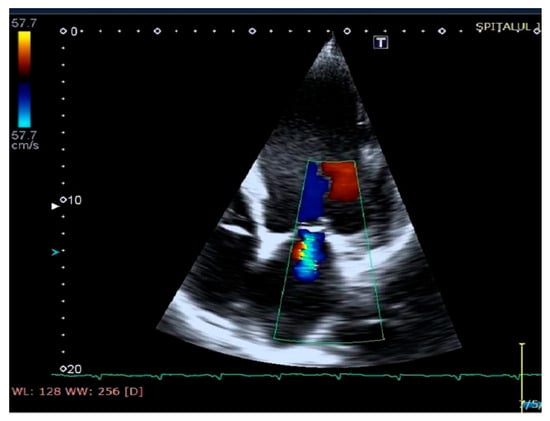

Figure 6.

Mitral regurgitation (highlighted as multicolored mosaic pattern, green and yellow), before therapy with a cardiac resynchronization device.

Figure 7.

Mitral regurgitation (highlighted as multicolored mosaic pattern, green and yellow), after therapy with a cardiac resynchronization device.